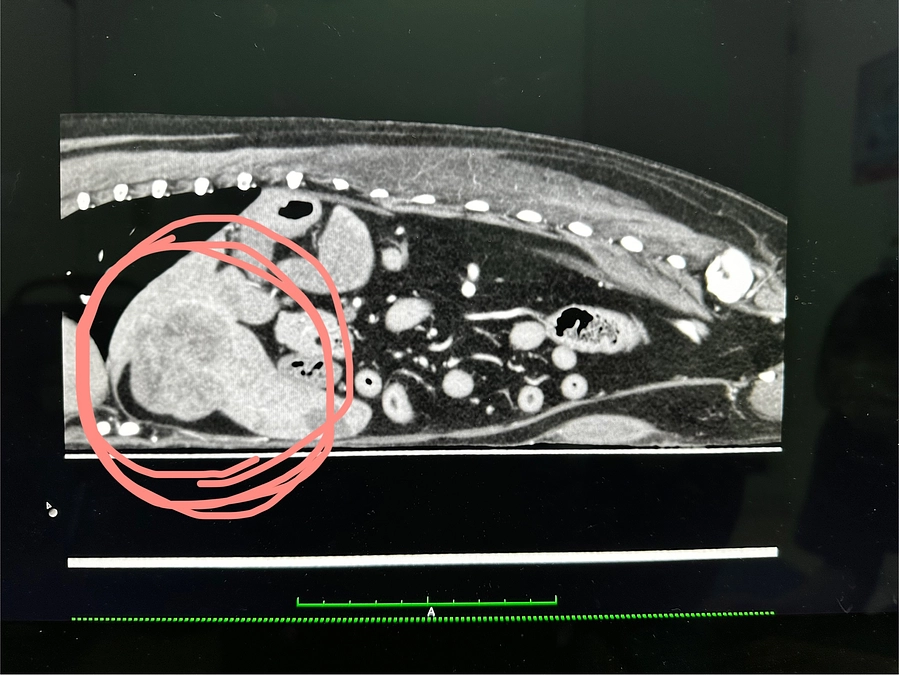

ビーデルの癌は良性(軽度)でした!

本日抜糸&腫瘍の解析結果を聞いてきました!

結果癌ではあるが悪さをする可能性が低いものだと判りました!

12月に撮ったCTには鼻に異常は見られなかったから腫瘍の可能性は低い、

おそらく歯周病(口鼻腔瘻)だろうということでした。